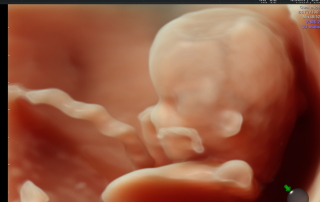

פרופ' ישראל מייזנר, הינו גינקולוג מבכירי הרופאים המומחים בארץ ובעולם בתחום האולטראסאונד, ובביצוע פעולות פולשניות תחת בקרת אולטראסאונד כגון בדיקות סיסי שליה ומי שפיר, דיקור ציסטות, עירוי דם לעובר ועוד.

לפרופ' מייזנר מרפאה פרטית בסביון בה הוא עורך לנשים בהריון בדיקות אולטרה סאונד הכוללות בדיקות שקיפות עורפית סקירות מערכות ויעוצים וחוות דעת למומים מולדים.